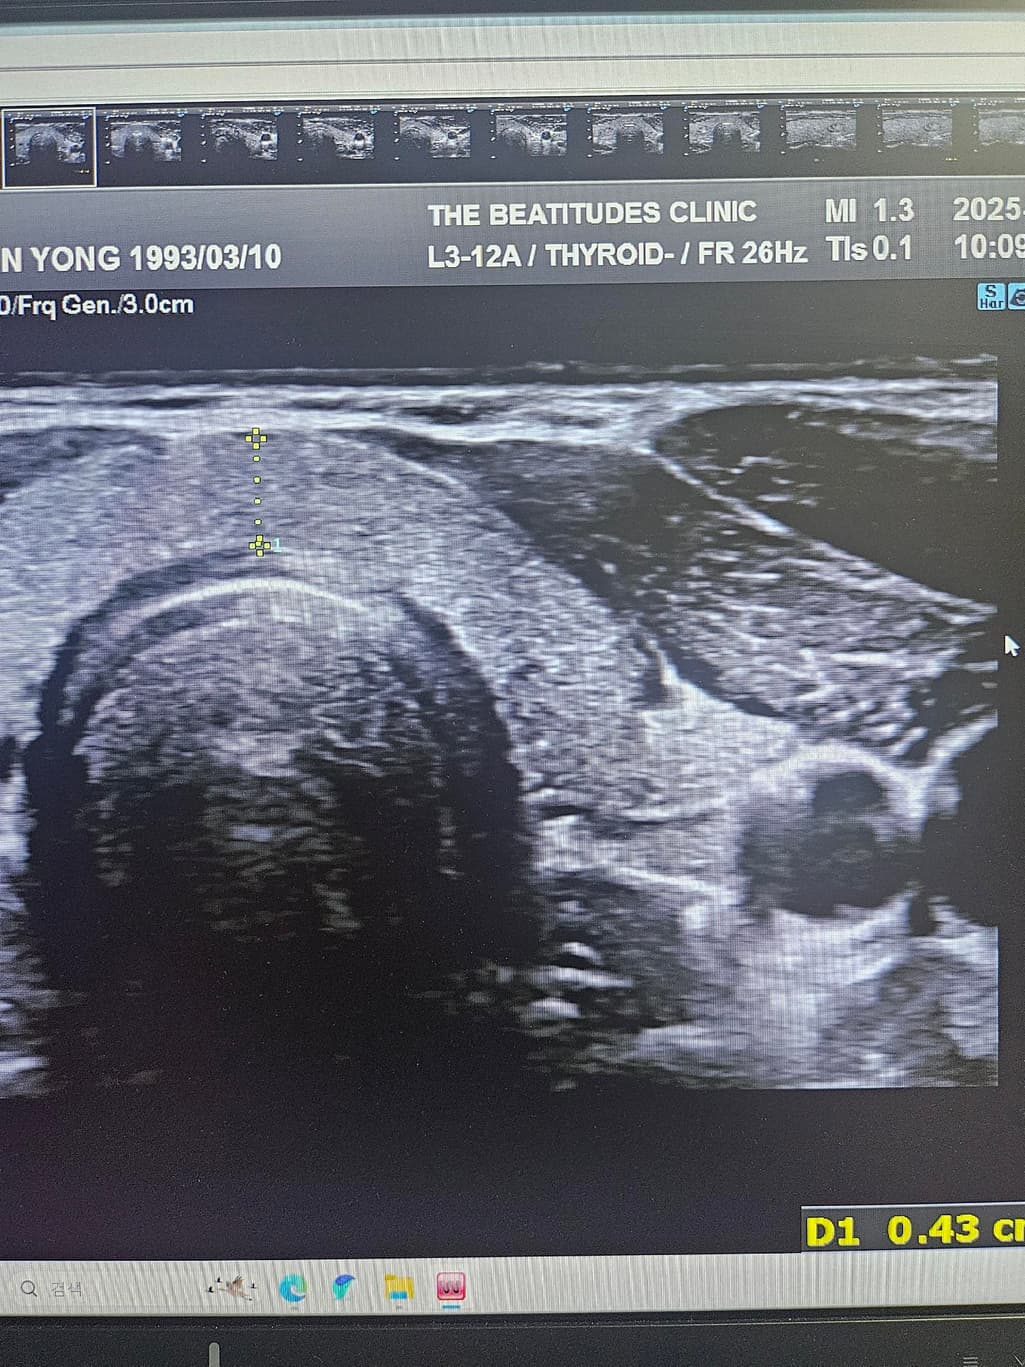

갑상선초음파하고 세침검사 권유받았는데 위의 세개의 사진은 같은 혹이 맞는건가요? 1개 있다고 얘기해줘서 봤는데 사이즈가 이렇게나와서 가로 세로 폭 값인건지 여쭤보고싶습니다

• 1번 째 사진

첫번째 사진과 세번째 사진의 경우 같은 결절로 보입니다.

모양만 본다면 갑상선암이 많이 의심되는 상황은 아닙니다.

초음파에서 첫번째, 세번째 사진의 급성 연골 오른쪽에 위치한 오른쪽 갑상선에 동그란 혹이 관찰되며 사진으로는 사이즈를 정확하게 구하기 어렵지만 1.5 cm 이상으로 보이며 혹 안에 균질하지 않은 모습으로 악성 혹은 양성이라고 해도 정기적으로 관찰해야 하는 종양으로 보여 조직 검사를 받는 것은 필요한 것으로 보입니다. 갑상선 종양은 다른 종양에 비해 예후가 좋아 적절한 치료를 받으면 대부분 완치가 가능합니다